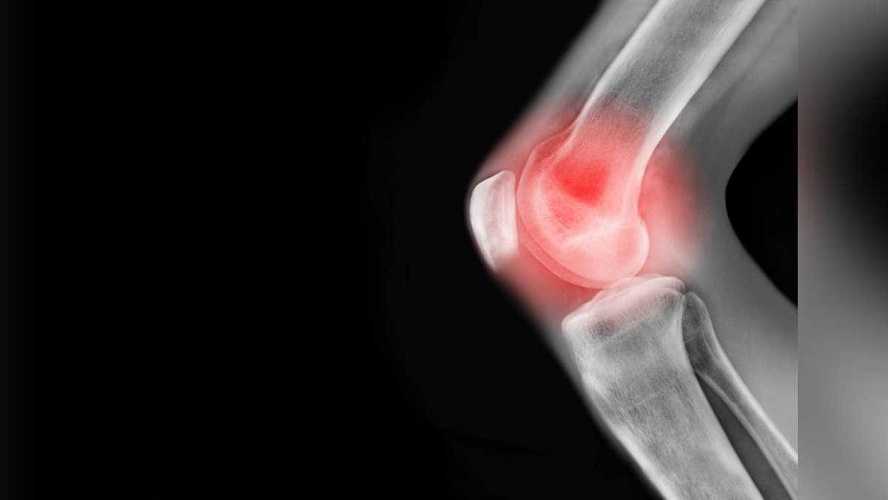

Con el paso de los años el cuerpo va perdiendo algunas características y empieza a padecer de dolores, uno de los más comunes es el de las articulaciones, especialmente de la rodilla. Esto se puede dar por un sobre esfuerzo, una lesión, ruptura de ligamento o desgarro del cartílago, de acuerdo con información de Mayo Clinic.

El portal también reveló algunas afecciones médicas que provocan el dolor de rodilla y estas son las más frecuentes:

Lesión del ligamento cruzado anterior. La lesión del ligamento cruzado anterior es el desgarro de ese ligamento, que es uno de los cuatro ligamentos que conectan la tibia con el fémur. La lesión del ligamento cruzado anterior es particularmente frecuente en las personas que juegan al básquetbol, al fútbol o a otros deportes que requieren cambios repentinos de dirección.

Fracturas. Los huesos de la rodilla, incluso la rótula (patela) se pueden fracturar durante una caída o una colisión automovilística. Además, las personas cuyos huesos se han debilitado por la osteoporosis pueden, a veces, sufrir una fractura de rodilla simplemente por pisar mal.

Desgarro de menisco. El menisco es un cartílago gomoso y duro que actúa como amortiguador entre la tibia y el fémur. Si se gira la rodilla en forma repentina mientras se carga peso sobre ella, se puede desgarrar el menisco.

Bursitis de la rodilla. Algunas lesiones de rodilla producen inflamación en las bolsas sinoviales, que son los pequeños sacos de líquido que amortiguan la parte exterior de la articulación de la rodilla y permiten que los tendones y los ligamentos se deslicen suavemente sobre la articulación.